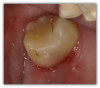

Figure 3a and Figure 3b show a failing composite with stress fractures and interproximal decay. The patient was not in a situation to do an indirect restoration, so the practitioner did a direct composite with good strength and wear characteristics until an indirect restoration could be performed. The composite used in this case is the Kerr SimpliShade Bulk Fill Packable, which in the author's experience also offers good blendability and polishability with good adaptation. Some of the discoloration interproximally is from the bleeding after the rubber dam was removed-which quickly self-resolved.

Fig 3a. A direct composite using Kerr SimpliShade Bulk Fill Packable.

Fig 3a.

Fig 3b. A direct composite using Kerr SimpliShade Bulk Fill Packable.

Fig 3b.